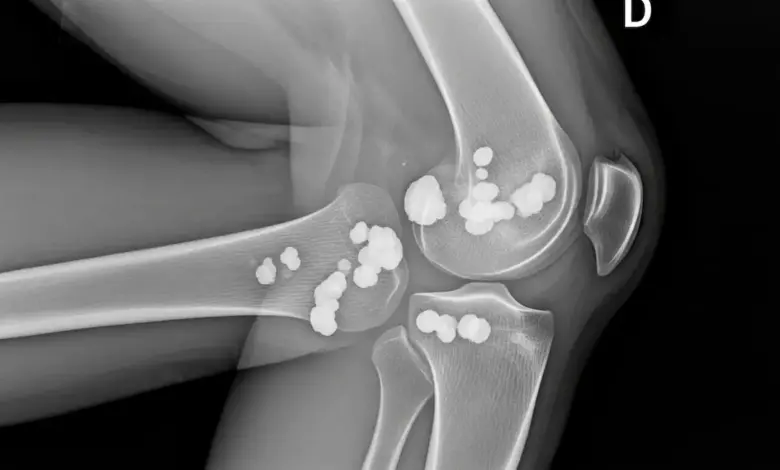

- Radiografia, que pode mostrar focos de calcificação;

- Ultrassonografia, útil para avaliar tendão, inserção e partes moles;